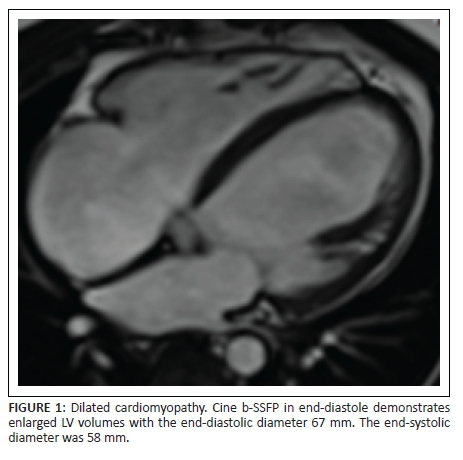

DCM refers to LV systolic dysfunction with concomitant LV dilation; RV dilatation may be present. In 50% of cases, the diagnosis remains unknown; up to 30% have a familial association to known genetic abnormalities.12 Chronic myocarditis has been implicated in the aetiology of DCM.12

CMR provides accurate evaluation of biventricular EFs, volumes and mass assessment, and the pattern of LGE allows the exclusion of an ischaemic cause, typically subendocardial or transmural enhancement. LGE provides prognostic information and acts as a gatekeeper role to coronary angiography.13

Figure 1 and Figure 2 provide the representative imaging features of DCM.